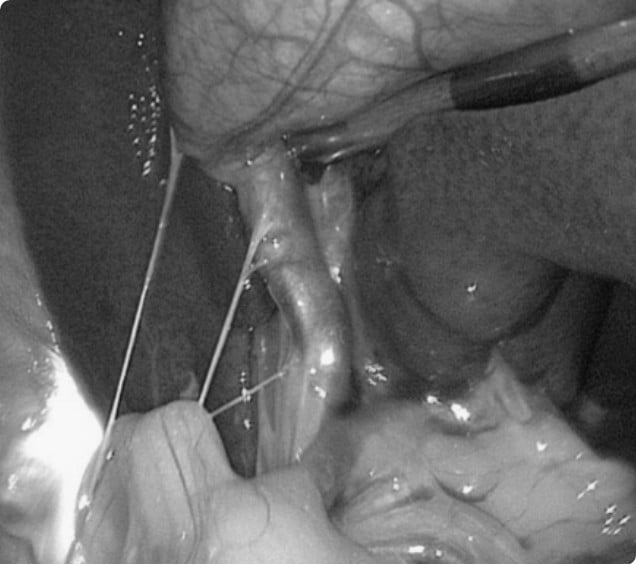

복강경 담낭절제술은 복부에 작은 절개창만을 통해 카메라와 기구를 삽입하여 담낭을 제거하는 최소침습 수술.

넓은 개복이 필요하지 않아 통증과 회복 부담이 줄고,

감염 위험까지 낮춘 안전한 치료 방법.